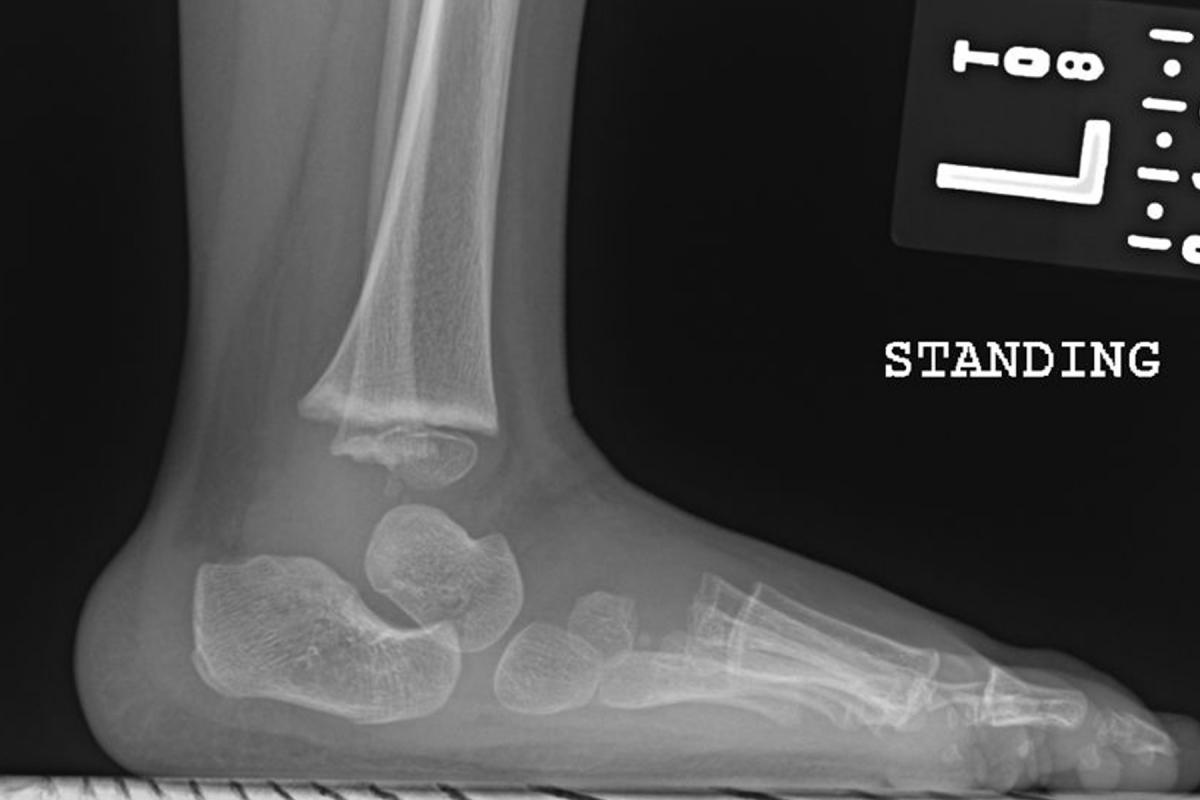

Briefly, treatment begins with identifying the morbid anatomy. Radiographs are unreliable and unlikely to enter into initial decision-making so they are rarely necessary to begin treatment. The surgeon initially palpates the ankle area at the malleoli and then brings his or her fingers and thumb distally to identify the talar head, noting that the navicular is displaced on the plantar and medial aspect of it.

Fourth, until one has correctly aligned the forefoot and rearfoot, it is inappropriate to treat ankle equinus. Doing so has several undesirable consequences. Casting an unyielding equinus deformity will eventually damage the talar trochlear surface, making it flat and causing it to lose its sphericity. Ankle dorsiflexion will be mechanically limited. Rocker bottom deformity results from attempting to dorsiflex the rearfoot prematurely against the unyielding tendo-Achilles. Inflexible equinus causes the midfoot to dorsiflex against the rearfoot along the lateral column while the calcaneus remains in a plantarflexed position. This breaches the foot through the calcaneocuboid joint as well as the fourth and fifth metatarsal cuboid articulations.